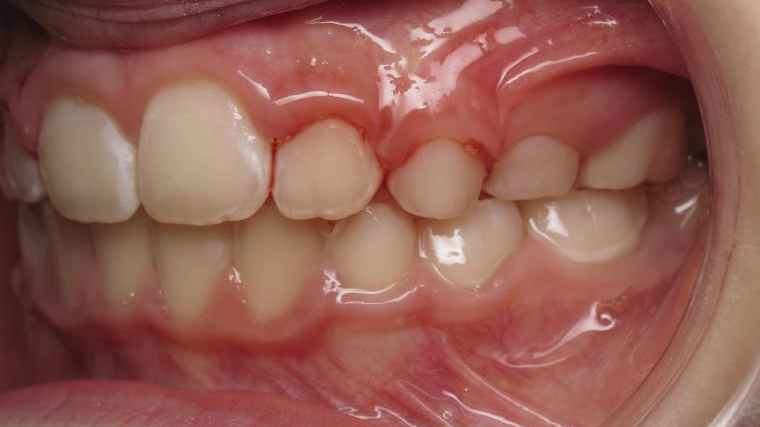

6 décalage sagittal 5 ans

Décalage entre les dents d avant en arrière